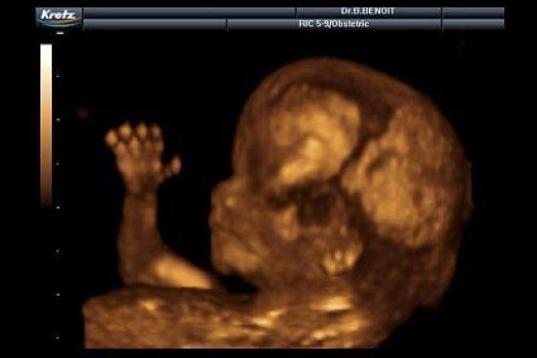

En esta galería puedes ver en fotos como es el desarrollo de un feto de semana en semana:

Desarrollo del feto, en fotos

Ver la galería